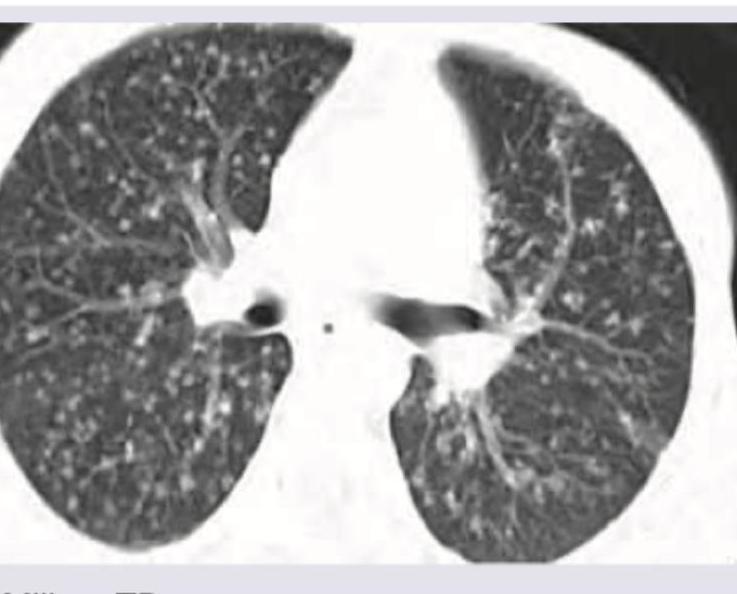

The given CT scan chest shows presence of:

Explanation: ***Miliary TB*** - The CT scan shows numerous tiny, **evenly distributed nodules** throughout both lung fields, measuring 1-5 mm in diameter, which is characteristic of **miliary dissemination** of tuberculosis. - This pattern results from the hematogenous spread of *Mycobacterium tuberculosis*, leading to the formation of small granulomas resembling millet seeds. *Endobronchial TB* - Endobronchial TB involves the **tracheobronchial tree** and typically presents with features like **bronchial narrowing**, wall thickening, or obstruction, which are not the predominant findings here. - While it can be associated with parenchymal disease, its primary manifestations are within the airways, not diffuse miliary nodules. *Bronchocele* - A bronchocele, also known as a **mucoid impaction**, appears as a **dilated bronchus** filled with mucus, often seen as a finger-in-glove appearance on imaging. - This is a localized finding and does not correspond to the widespread nodularity seen in the image. *Central bronchiectasis* - Central bronchiectasis refers to the **irreversible dilation of central bronchi**, often associated with conditions like allergic bronchopulmonary aspergillosis (ABPA). - It would appear as widened, thick-walled airways, rather than the diffuse small nodules characteristic of miliary disease.